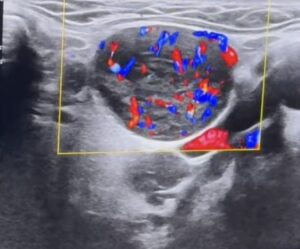

Nang Buồng Trứng Xuất Huyết

NANG BUỒNG TRỨNG XUẤT HUYẾT Bs. Lê Lý Trọng Hưng Bs. Nguyễn Thị Thu Anh...